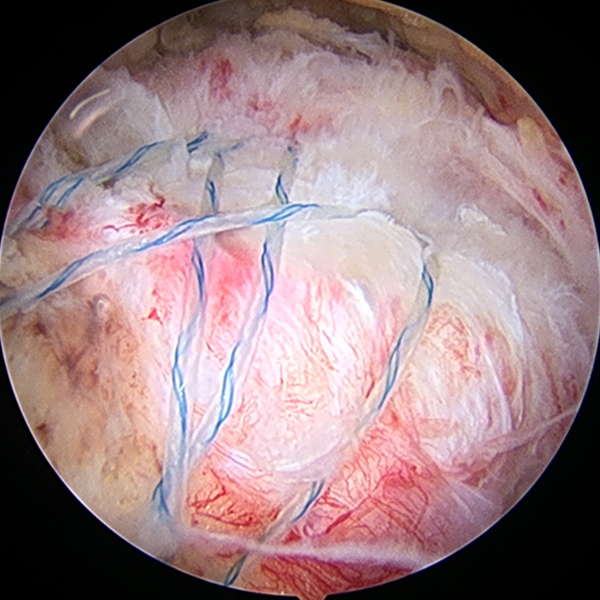

整形外科における手術の役割 肩腱板断裂治療のアルゴリズム 不全断裂 小断裂 中~大断裂 一次修復不能広汎性断裂 保存療法(リハビリ:運動療法/物理療法) 手術療法 関節鏡下腱板修復術 腱移行術、腱移植術、リバース型人工関節 腱板断裂の治療の基本は保存療法ですが、それが反応しない場合には、関節鏡下腱板修復術が適応されます。 修復前 修復後 関節鏡下腱板修復術は「肩に小さな穴を数か所開け、関節鏡で中をのぞきながら縫い合わせる方法」で、私の得意分野です。 不全断裂 小断裂 中~大断裂 一次修復不能広汎性断裂 保存療法(リハビリ:運動療法/物理療法) 手術療法 関節鏡下腱板修復術 腱移行術、腱移植術、リバース型人工関節 縫いきれないほどの大きな断裂には、腱の移植や人工関節が必要になります。 手術を望まない方へは、間葉系幹細胞を用いた再生医療の提供に取り組んでいます。